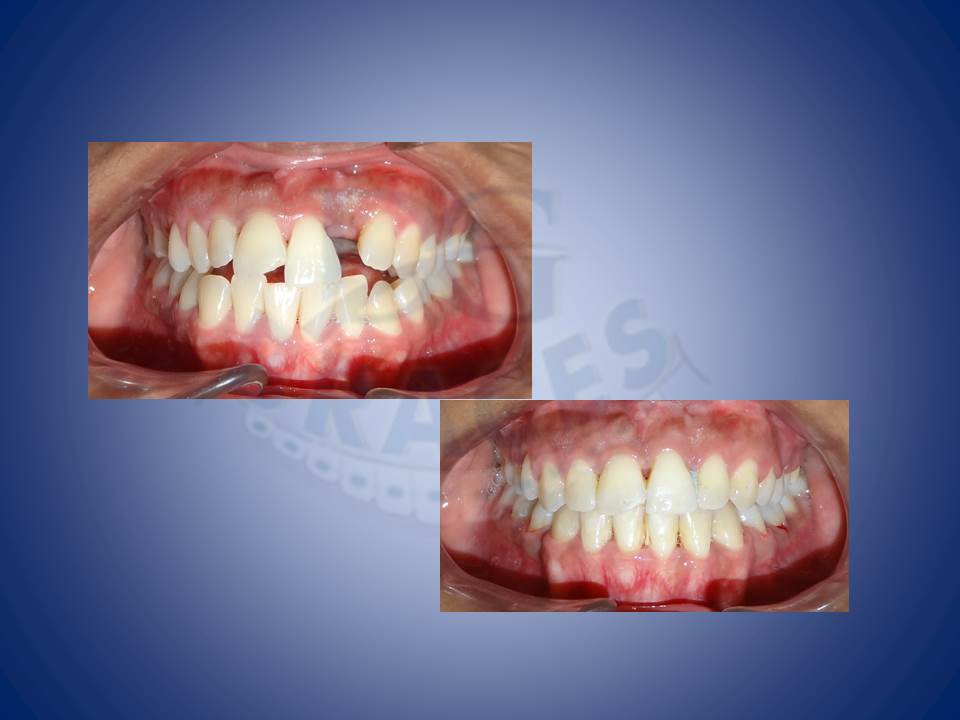

1.Crooked teeth are most often something which patients feel the need to be corrected. This is how we do it!!!